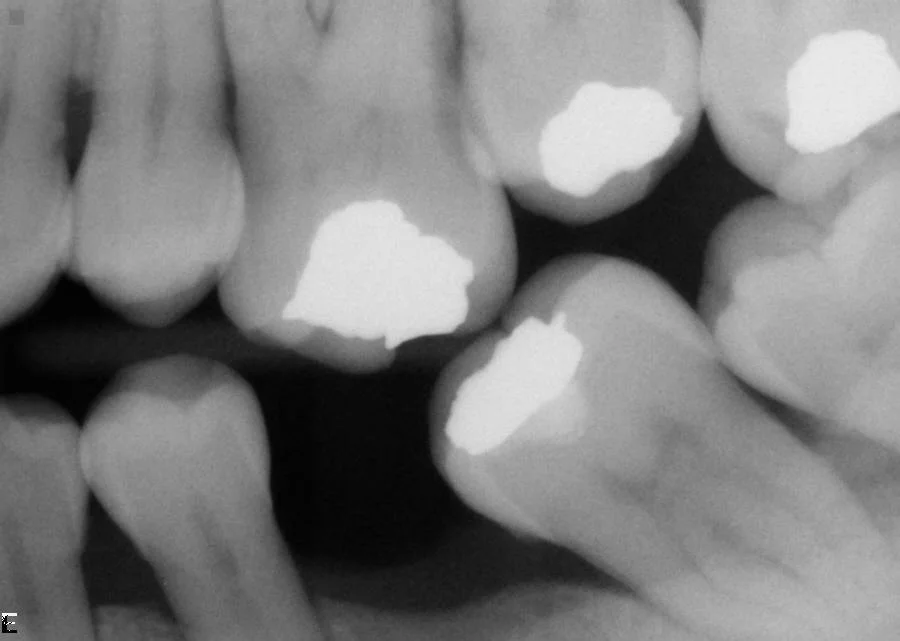

Before: Infected lower left teeth